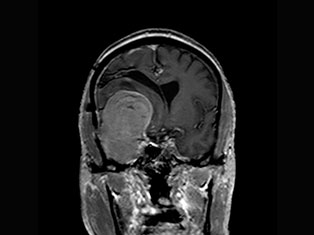

Brain Tumors

A brain tumor is a mass or growth of abnormal cells in your brain. Many different types of brain tumors exist. Some brain tumors are noncancerous (benign), and some brain tumors are cancerous (malignant).